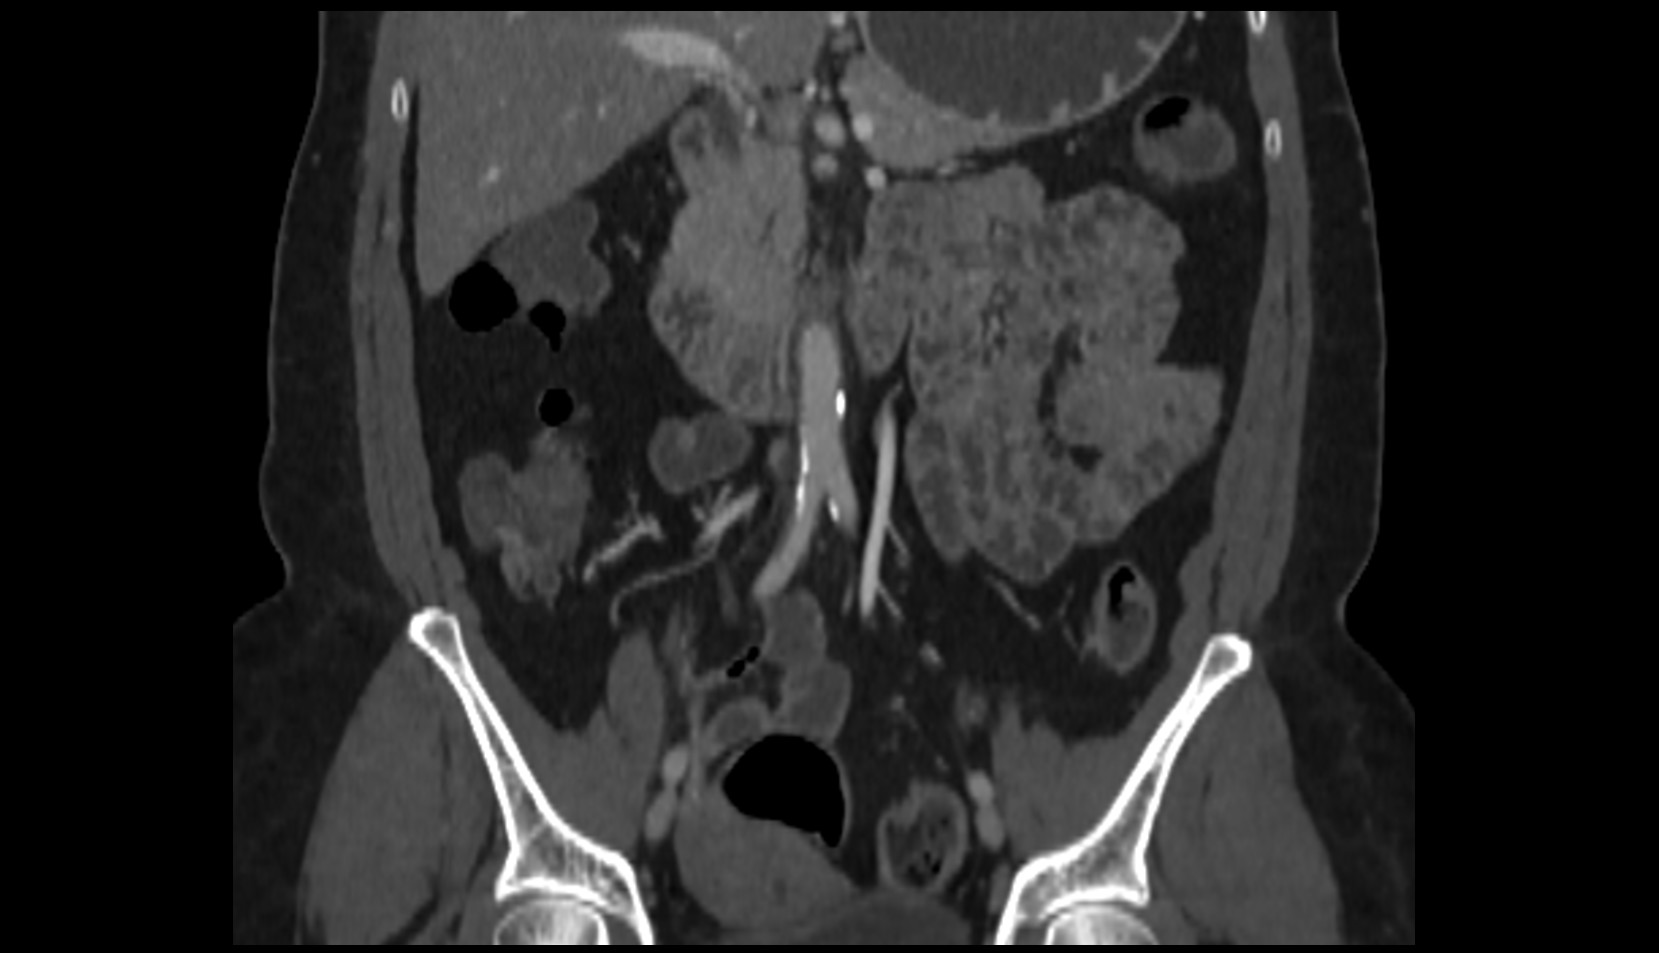

- kidneys

- Right kidney

- Left kidney

- Kidney cortex (Renal cortex)

- Renal capsule

- Renal medulla

- Renal pyramids

- Renal artery

- Renal vein

- Left renal vein

- Right renal vein

- Aortic bifurcation

- External iliac artery

- Internal iliac artery

- common iliac artery